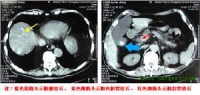

实验室检查可发现血液浓缩、低血钾、低血氯和碱中毒。立位腹部X线片可见左上腹巨大液平面和充满腹腔的特大胃影及左膈肌抬高。

实验室检查可发现血液浓缩、低血钾、低血氯和碱中毒。立位腹部X线片可见左上腹巨大液平面和充满腹腔的特大胃影及左膈肌抬高.